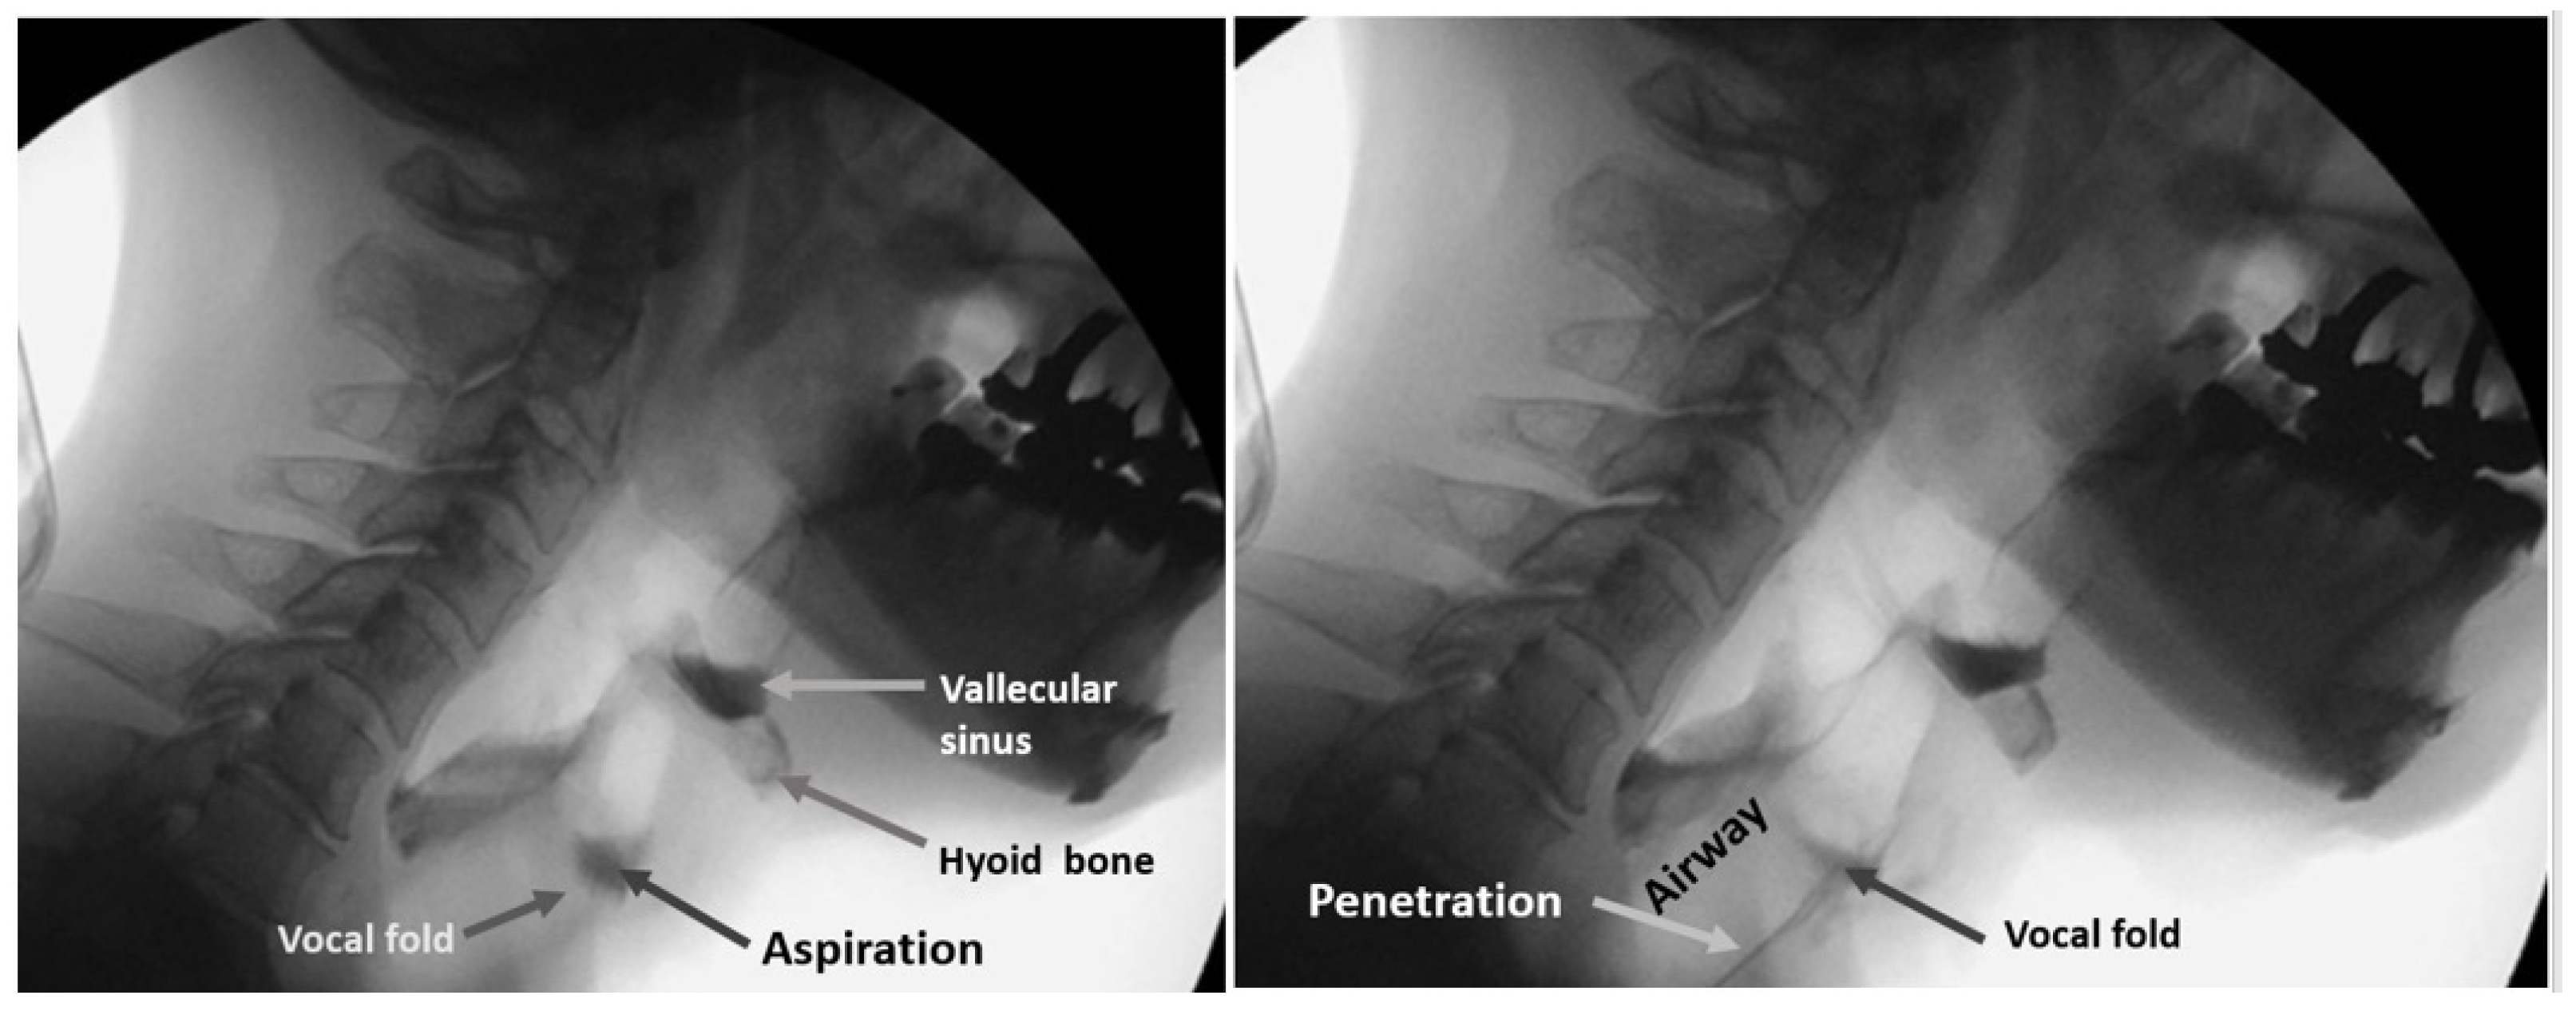

The protocol for the VF of each patient involved presentation of swallows with 1 to 3 mL standard meals with barium without any instruction for swallowing. All three or four dentists involved in the examination inspected laryngeal invasion, aspiration, and accumulation of epiglottis valley/pyriform sinus. At least two of the three or four observers were qualified as Board Certified Fellows of the Japanese Society of Dysphagia Rehabilitation. The examiners in the VF room can miss the findings on the monitor because they are concentrating on the patient’s condition. In our hospital, one or two dentists are in the VF room, and the others are outside the VF room, checking the monitor, to obtain consensus. Figure 8 shows the sample VF images of aspiration (left image) and penetration (right image).

Figure 8.

Sample VF images. Left image shows the aspiration and right image shows penetration.

Observers recorded these findings on the VF exam chart. These VF exam charts were used for the classification of a dysphagia (+) case and (−) case. In this study, penetration and aspiration cases were treated as a dysphagia (+) case.